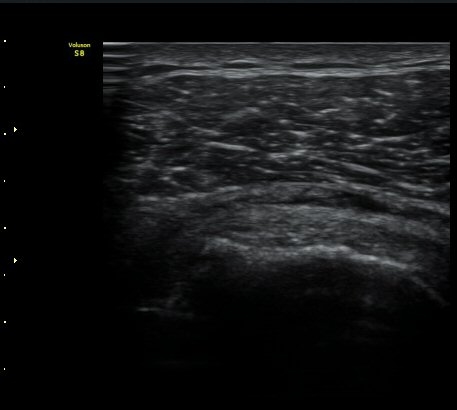

±Ø»ó°Ç Ⱦ´Ü¸é°Ë»ç½Ã ±Ø»ó°Ç ÀϺΠÀú¿¡ÄÚ ºÎÁ¾°ú ¹Ì¼¼ÇÑ °Ç ¿¬°á¼º ¼Ò½ÇÀÌ °üÂûµÊ(±×¸² 4, 5).

±×¸² 4)¿¡¼­ °üÀý¿¬°ñ°æ°è¸é ¡ÈÄ(articular interface sign)°¡ °üÂûµÊ.